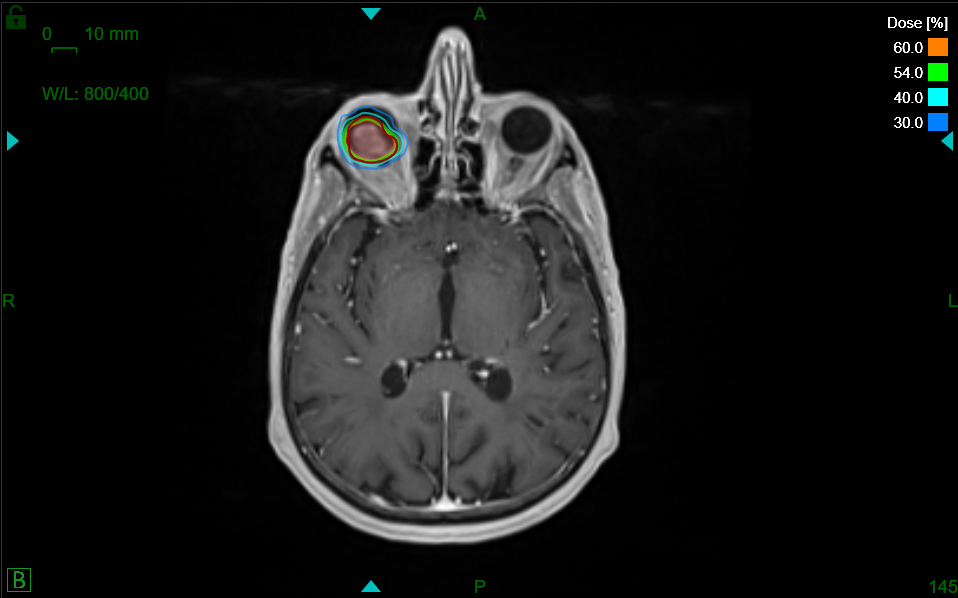

Schnell kommt die Frage nach möglichen Behandlungsformen auf. Eine Option ist die hochpräzise Radiochirurgie, welche die SNRC AG in Zürich auf dem neusten Stand der Technik mit dem ZAP-X® anbietet. Diese Form bietet den Betroffenen eine Alternative bzw. Ergänzung zur klassischen Operation oder der herkömmlichen, meist langwierigen Strahlentherapie.

Mit dem ZAP-X können Tumore, Metastasen und auch Krankheitsbilder wie Trigeminusneuralgie hochpräzise, effektiv, nachhaltig und bei gleichzeitiger Schonung des umliegenden, gesunden Gewebes therapiert werden. Die Behandlung erfolgt ambulant und ohne Narkose. Sie dauert ca. eine Stunde, ist absolut schmerzfrei und die Patienten können im Anschluss direkt nach Hause.